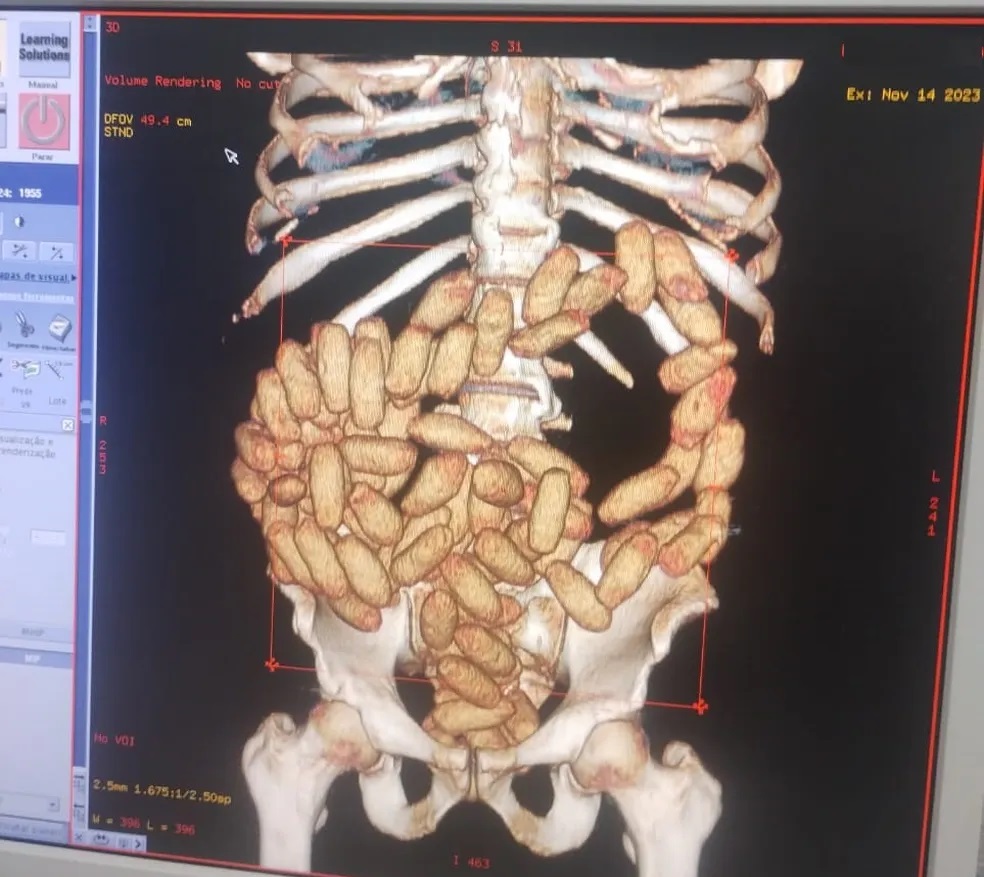

Seis homens de nacionalidade boliviana foram presos em flagrante, neste sábado, 25, em São Paulo, suspeitos de atuarem como ‘mulas’ do tráfico engolindo drogas para fazer o transporte Eles foram abordados por agentes da Polícia Civil a bordo de um ônibus de turismo procedente da Bolívia. Os seis suspeitos levavam no estômago um total de 454 cápsulas de cocaína, que pesaram 1,8 quilo da droga.

O veículo foi levado para a sede do Deic, em Santana, na zona norte da capital, onde todos os passageiros foram submetidos a exame de Raio X. Seis estavam com a droga no estômago.

Eles foram encaminhados para o pronto-atendimento da Santa Casa de Misericórdia, na Vila Buarque, onde receberam medicação para expelir a cocaína. Após a alta médica, os investigados foram autuados por tráfico de drogas e associação para o tráfico.